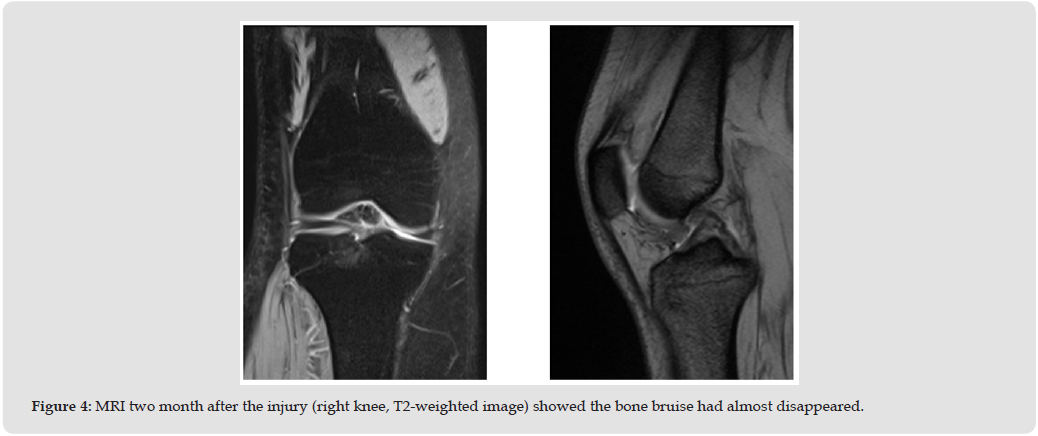

A 28-year-old female presented with severe right knee pain and gait disturbance. The symptoms began after a dog bumped her. She nearly fell, stepped forward with her right foot to brace herself, during which her knee gave way. She was taken to a nearby hospital where MRI revealed no significant findings (Figure 1). She returned to work, but her knee pain gradually worsened. One month later, a repeat MRI showed a bone bruise in the anterior tibial plateau (Figure 2). Her symptoms persisted for approximately 2 months. Therefore, prompting referral to our department. Her past medical and family histories were unremarkable. Physical examination revealed no swelling, or effusion, but tenderness was noted in the right knee. The range of motion was 0°-145°. McMurray test for meniscal injury were negative. The anterior and posterior drawer tests, as well as varus and valgus stress tests, were normal. The Lachman test was positive. The patient had no patellofemoral symptoms. Her Lysholm knee score was 42. Plane radiographs showed no bony or soft tissue abnormalities, including intra-articular loose bodies. Computed tomography revealed no subchondral bone loss (Figure 3). MRI confirmed the presence of a bone bruise in the anterior tibial plateau.

In this case, MRI at the time of injury revealed no bone bruises. However, 1 month later, when the patient’s pain had worsened, bone bruise appeared on MRI. Moreover, as the pain subsided, the bone bruise also resolved. Traumatic bone bruises typically result from direct injury that disrupts the trabeculae of subcortical bone, leading to the accumulation of interstitial fluid and hemorrhage within the extracellular space [4]. On MRI, bone bruises are identified by subcortical hypointense signals on T1-weighted images and hyperintense signals in T2-weighted images, reflecting a localized increase in fluid content [5]. Bone bruises of the tibiofemoral joint serve as a footprint of the dynamic forces within the joint at the moment of ACL rupture, offering insights into the mechanisms of injury [6-8]. Characteristic bone bruise patterns in ACL injuries have been described, with the lateral tibial plateau (LTP) and lateral femoral condyle (LFC) being the most common sites. Notably, the posterior LTP and central LFC are most frequently affected [9-13]. Studies have reported that a higher incidence of bone bruises in the lateral compartment suggests the presence of valgus stress during the ACL injury, which may lead to opening of the medial joint space [6,14].